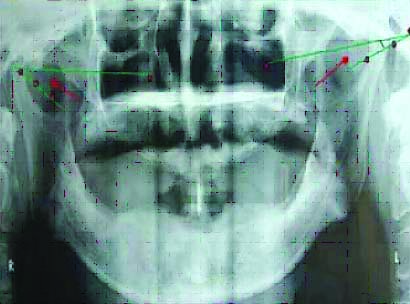

A panoramic radiograph was taken using orthopantomogram (PM2002CCPROLINE). All radiographs were made by the same operator and with the same radiographic unit; the image was acquired at 74 kvp, and 10 mA. Tracings were made of the images of each radiograph on tracing paper. Images were traced for Frankfort horizontal plane which passes through the lowest point in the margin of the orbit and highest point in the margin of auditory meatus. Outline for most superior point on the articular eminence and inferior point on the articular tubercle just adjacent to zygomatic arch were traced [Table/Fig-4]. A line was drawn connecting most superior and inferior points of curvature representing the mean curvature line [Table/Fig-5]. The angle was measured between mean curvature line and the reference line, each measurement was repeated twice, twenty panoramic radiographic images were traced independently before making interpretation, and the data were subjected to the statistical analysis [Table/Fig-5].

Panoramic radiograph showing landmark used.

Tracing of line AB joining height of superior curvature A and inferior curvature B, representing inclination of articular eminence is angle made by intersection of mean curvature line and horizontal reference line.